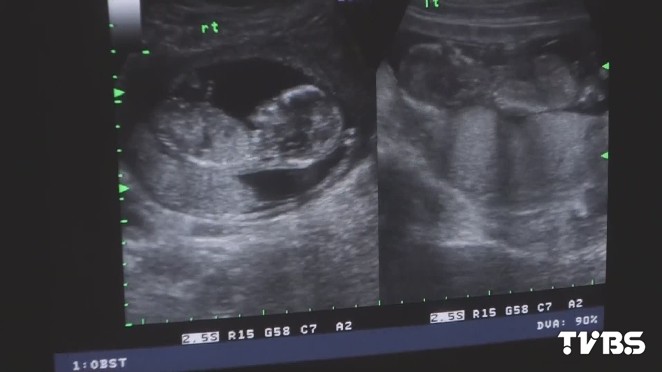

台灣有每年約有1萬多人接受試管嬰兒療程,彰化基督教醫院與台大醫院等合作,研發出基因晶片快篩技術,可以在9個小時內篩檢出染色體正常的胚胎,而且因為時間短胚胎不用冷凍,比起現在可以縮短1-2週時間,減少胚胎因冷凍受損機率,受孕成功的機率也提高,懷孕率可提高到88%。

圖/TVBS資料畫面